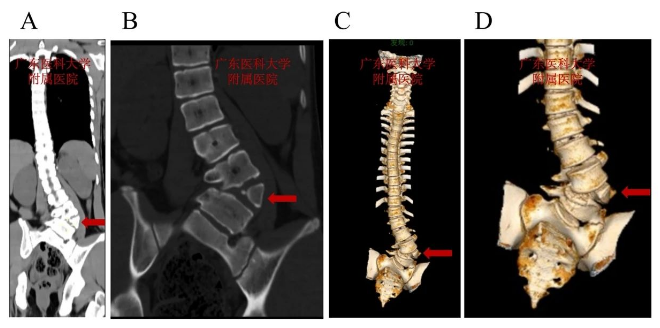

术前脊柱CT:L4呈楔形半椎体畸形,腰弯以L4半椎体为顶锥明显向左侧凸

术前脊柱CT:见L2左侧椎弓根缺如

该青少年患者,腰骶段半椎体畸形,先天性脊柱侧凸,腰弯(L3-L5)Cobb角73.40°,脊柱侧凸角度大,为重度先天性脊柱侧凸,同时患者L2左侧椎弓根缺如,脊柱侧凸矫形手术难度大。根据患者具体情况,科主任魏波教授组织全科讨论评估患者病情,做了详细的术前评估,并制定了完善的手术方案及策略。